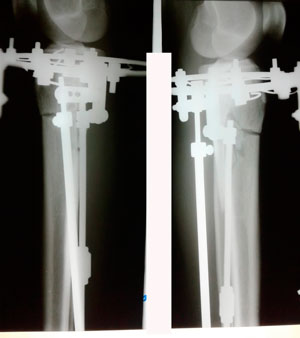

в процессе круток

Вложения

image-13-07-20-09-15.jpg